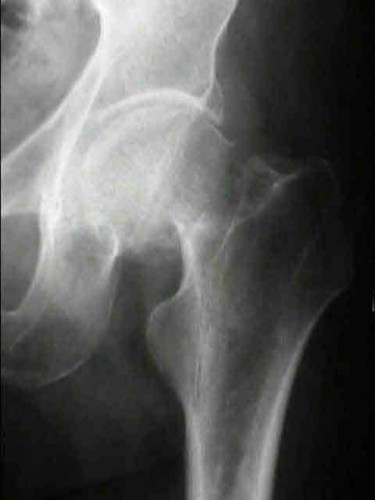

A 12-year-old obese boy presents with vague left thigh and knee pain. He is diagnosed with a Slipped Capital Femoral Epiphysis (SCFE) as seen in similar clinical scenarios.

During percutaneous in-situ fixation, unrecognized penetration of the guide wire into the hip joint occurs. What is the most likely specific complication resulting from this technical error?

Explanation

Chondrolysis is a severe complication of SCFE characterized by rapid destruction of the articular cartilage. While it can occur idiopathically, its most established iatrogenic cause is unrecognized intra-articular hardware penetration. The 'approach-withdraw' fluoroscopic technique is required during pinning to assure pins are entirely intraosseous. Avascular necrosis (AVN) is usually due to damage to the epiphyseal blood supply (retinacular vessels) secondary to the initial displacement, forceful closed reduction, or posterosuperior pin placement.